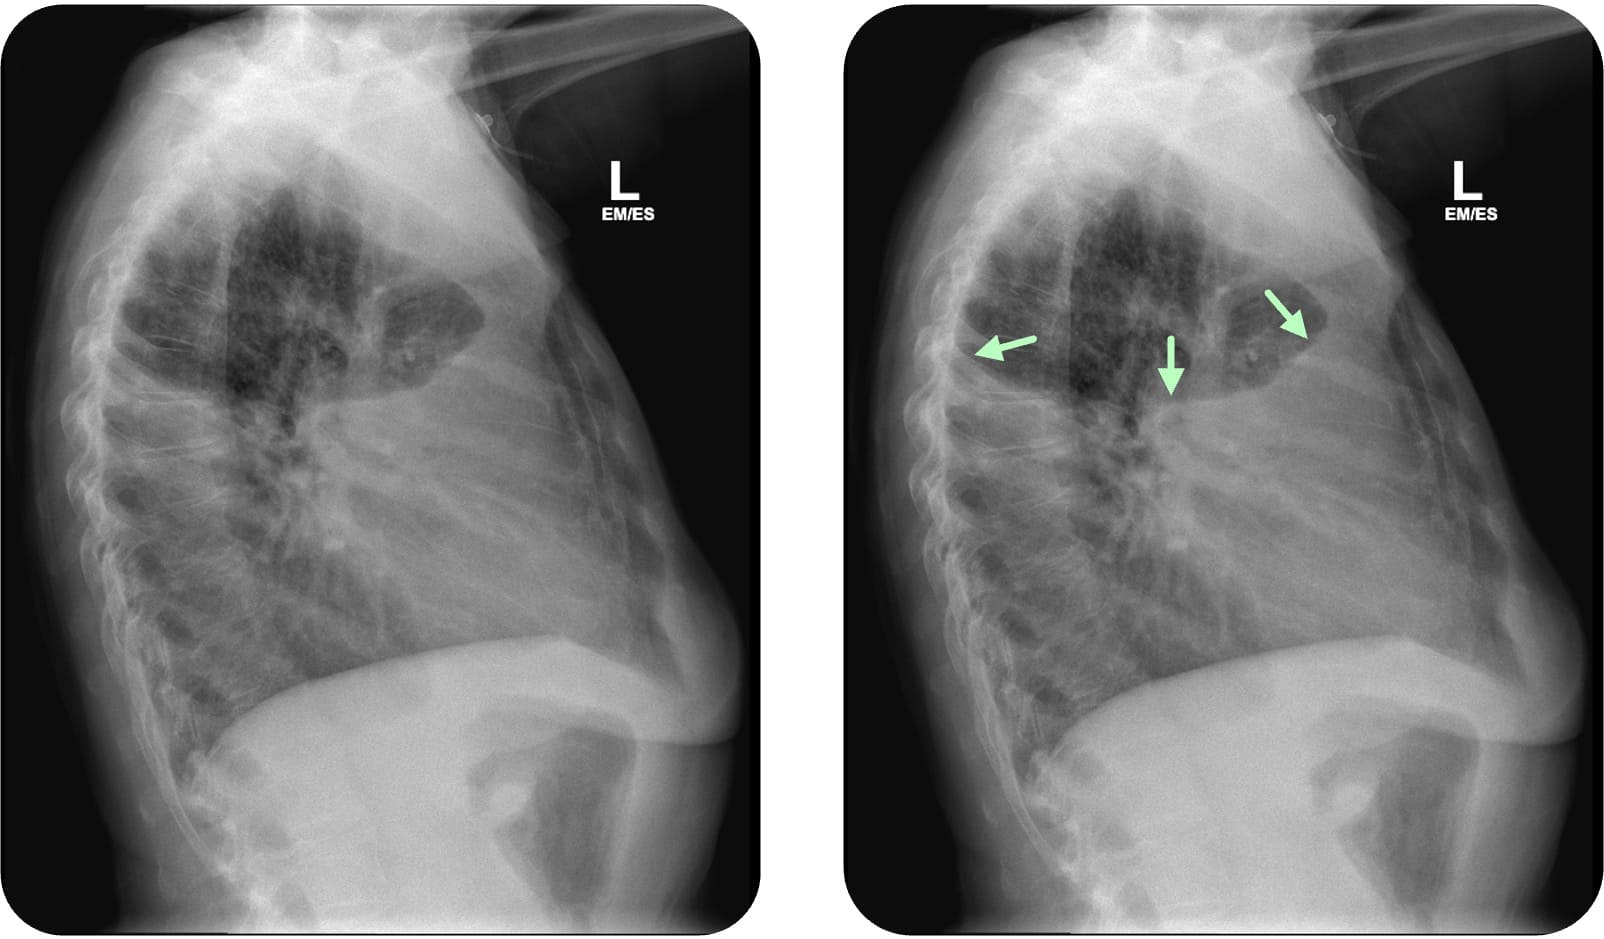

Interlobärerguss

Sonderformen sind der Interlobärerguss, der subpulmonale Erguss und der abgekapselte Erguss. Beim Interlobärerguss befindet sich die Flüssigkeit im Lappenspalt (Fissura obliqua oder horizontalis). Sie ist meist oval begrenzt („Zitronenform“) und insbesondere in der seitlichen Aufnahme gut beurteilbar. Er kann einen Rundherd

Case courtesy of Davison Dzamatira, Radiopaedia.org, rID: 99009